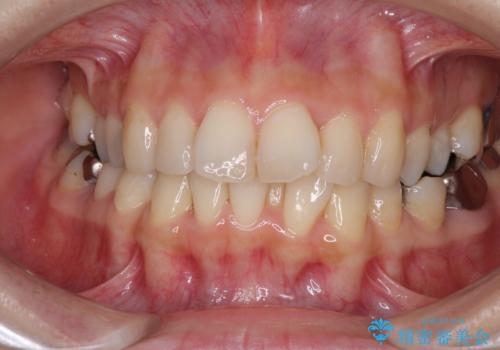

- 上下のデコボコと奥歯の咬みにくさを気にして来院された患者様です。

上顎骨の幅が下顎骨よりも小さいので、拡大装置により骨幅を広げて上下関係を改善し、その後インビザラインにて歯並びを整えることとしました。

上下の骨幅を改善したことで、スムーズに歯列矯正を行うことができました。

矯正治療中に近医で銀歯を外す治療を開始したため、治療後に奥歯の咬み合わせが不十分ですが(こちらは近医での治療により改善するとのこと)、歯列と咬み合わせが改善され、患者様には大変満足していただきました。